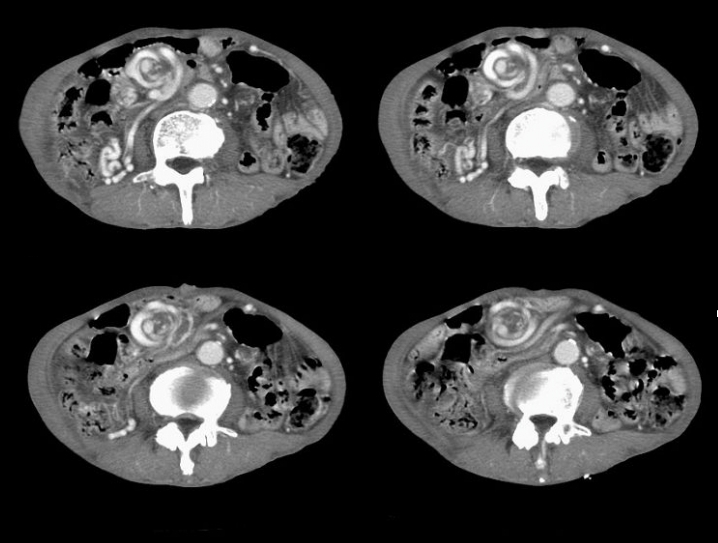

1、靶征(肠套叠)

是肠套叠最常见的特征性CT征像,为肠套叠长轴与CT扫描层面垂直时的表现,反映了套叠的各层肠壁、肠腔及肠系膜间的关系。典型排列为自外向内分别代表鞘部外层肠壁、鞘部肠腔内造影剂、鞘部内层肠壁、偏心性套入部肠系膜、套入部肠壁、套入部肠腔内造影剂。

肠套叠指:一段肠管及与其相连的肠系膜(套入部)被套如其相连的一段长管内(鞘部),导致肠内容物通过阻碍。婴儿由于大肠与小肠管径之比例相差大。故小肠易陷入大肠而被套牢。少数肠套叠可能来自某些器质性病变如美凯尔憩室、肠息肉、异位胰腺小结、血管瘤、异物、复制肠管、淋巴增生、肿瘤、寄生虫等,其中以美凯尔憩室最多,过敏性紫斑也常会合并肠套叠,大于2岁的小孩发生肠套叠,一定要考虑到这些病变。大于5岁的病例中,则以淋巴瘤为最多;成人肠套叠小肠多见,常伴发良性病变;结肠型肠套叠则更多由恶性病变继发。良性病变有脂肪瘤、平滑肌瘤、血管瘤、神经纤维瘤、腺瘤样息肉、美克尔憩室、术后粘连机场动力性病变等;恶性病变有转移瘤、腺癌、类癌、淋巴瘤及平滑肌肉瘤等。由于肠套叠长轴与CT扫描层面的角度不同,表现各异。

如扫描层面和迂曲的肠道相平行时,表现为彗星尾征或肾形征:即套叠近端肠系膜血管牵拉聚拢的征象。一般情况下,慧星尾征均与肾型肿块相伴出现。该肾形肿块为套鞘部游离缘与套入部近端肠管及肠系膜的CT斜切面图像,其中游离的套鞘呈弧形围绕套入部,形状若肾轮廓外形,而套入部近端肠管、肠系膜形状若肾蒂。此时,所谓慧星尾征的组成还应包括套入近端肠管。如果套叠的肠管与CT扫描垂直,则呈靶形征,即肿块影表现为圆形或类似环形。通常在肿块内可分辨出层样结构,推测可能是继发于套入部和鞘部间的液体或是肠壁水肿造成密度对比,类似同心圆形;当套入部肠壁显著水肿坏死或套入部肿瘤周围浸润累及肠系膜,肠系膜血管及脂肪、套叠时间较长,套入部系膜血管受挤压时,静脉血液回流障碍,套入部肠壁充血水肿、变硬,形成不完全性肠梗阻,套叠以上肠管蠕动增强,可引起代偿性肠管扩张肥厚,并可见肠系膜连同其血管纠集、扭曲,形成“漩涡征”。